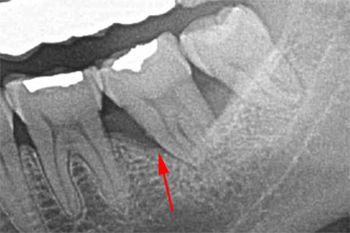

大臼歯の分岐部病変2度を含む浅く広い骨欠損

BEFORE(初診時)

向かって一番右側の奥歯と2番目の歯と3番目の歯の間の骨(矢印)が溶けてなくなっているのがわかるでしょうか?

”噛むと痛んで腫れている、過去に抜歯を薦められ不安なので診てほしい”と来院された女性の患者さんです。

AFTER ( 術中・術後 )

GTR法とエムドゲインの併用による再生療法により骨を再生しました(矢印)。

違いが解りますか?骨が再生されています。